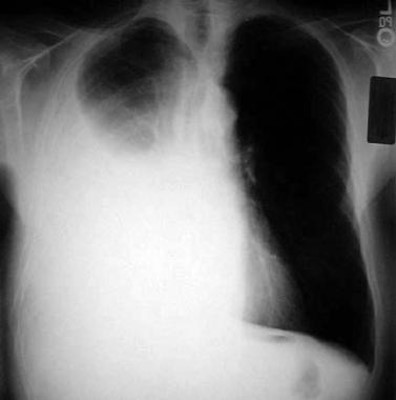

What is seen on the left?

Spontaneous Pneumothorax

(well demarcated line, right side is super black bc no lung tissue there)